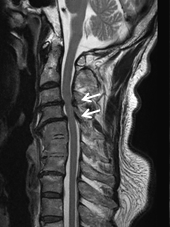

術前MRIでは多椎間で脊髄(灰色)を圧迫しています。後方手術施行後、脊髄への圧迫は改善しています。

頚椎椎間板ヘルニアを認め脊髄(灰色)を圧迫している状態です。骨移植を伴う頚椎前方固定術により症状は改善しています。